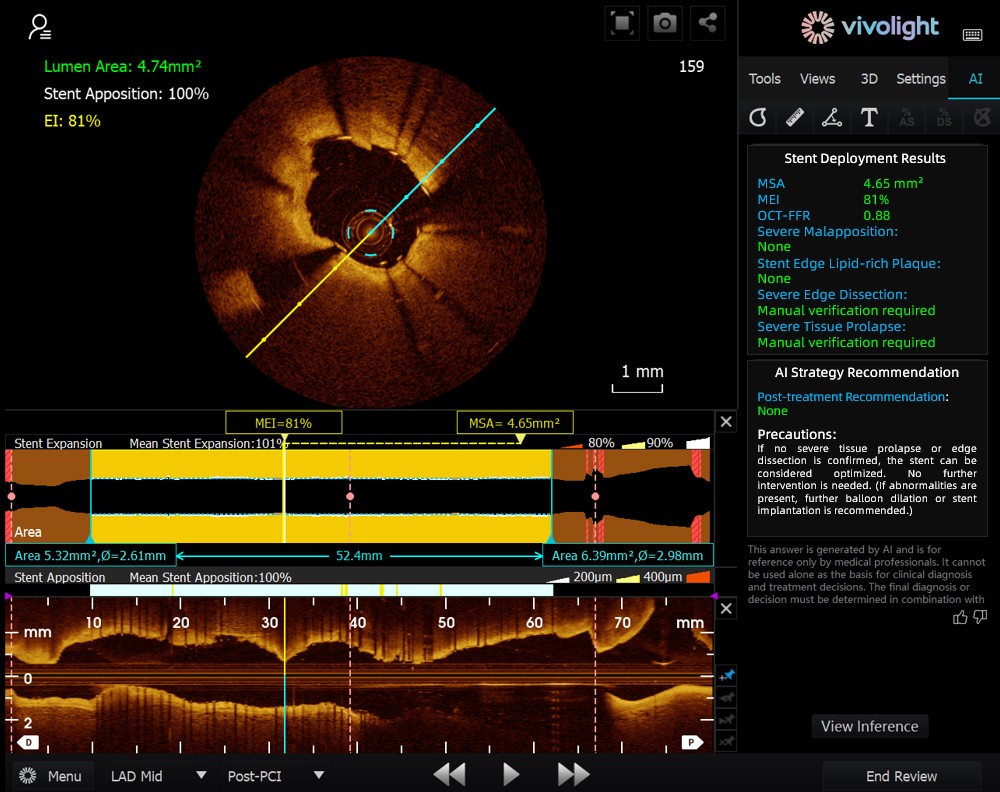

Sviluppato sulla base del sistema OCT di Vivolight Medical, AI-OCT è un sistema intelligente di supporto decisionale di nuova generazione per l'imaging intravascolare. Integra dati diagnostici di imaging intravascolare sparsi, tra cui diametro del lume, lesioni colpevoli, OCT-FFR e natura della placca, in strategie di trattamento complete e raccomandazioni attuabili. In quanto software di ricerca indipendente integrato nella piattaforma OCT, è sviluppato in collaborazione con diversi ospedali per creare versioni personalizzate su misura per specifiche esigenze cliniche.

Durante il forum all'avanguardia, gli esperti hanno sottolineato che il sistema AI-OCT rappresenta un passaggio radicale dalla "visualizzazione di immagini" alla "fornitura di piani di trattamento", affrontando le sfide del sovraccarico di informazioni e della complessità del processo decisionale nelle procedure interventistiche cardiache, che tradizionalmente si basano in larga misura sull'esperienza del medico. I principali vantaggi del sistema includono:

●Guida intraoperatoria in tempo reale: Organizza in modo dinamico le informazioni diagnostiche durante l'intervento chirurgico, fornendo parametri chiave e raccomandazioni cliniche.

●Processo decisionale basato sulle prove: Tutti i suggerimenti sono in linea con il consenso degli esperti e con le linee guida cliniche, garantendo rigore e affidabilità.

Il sistema AI-OCT adotta un'architettura "piccolo modello + big data + grande modello": i modelli piccoli consentono un'interpretazione precisa delle immagini, mentre i modelli grandi consentono un ragionamento clinico completo. Sfruttando database cardiovascolari di alta qualità e la tecnologia RAG (Retrieval-Augmented Generation), offre un supporto end-to-end, dalla valutazione della lesione allo sviluppo della strategia di trattamento.